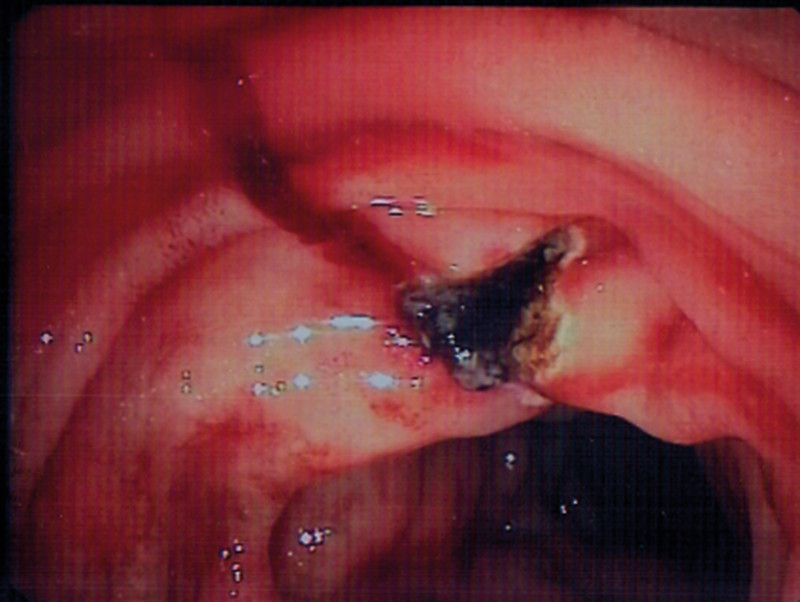

Pasienten ble gitt to nye poser med SAGMAN-blod, og man startet i tillegg behandling med traneksamsyre 1,5 g × 4 intravenøst. Ny gastroskopi på ettermiddagen samme dag viste fortsatt frisk blødning fra samme område i duodenum. Det ble igjen injisert fortynnet adrenalin, noe som resulterte i avtakende blødning. For å få bedre oversikt brukte man et ERCP-skop (optikk ut til siden). Man kunne da se sivblødning fra et punkt uten sårbunn (fig 1). Det ble injisert polidocanol 1 %, totalt 4,5 ml à 0,5 ml og deretter applisert argonplasmakoagulasjon (APC) nøyaktig mot det blødende punktet inntil full hemostase (fig 2).

Arteriell blødning fra en makroskopisk normal slimhinne ga en diagnostisk avklaring. Funnet var forenlig med Dieulafoys lesjon (exulceratio simplex), det vil si blødning fra en dilatert submukøs arteriole.